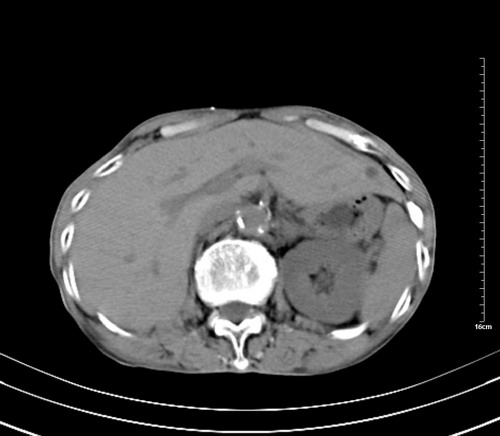

病人,女,79岁,主要因腹疼二月入院,彩超,肝,胆,脾,未见异常,胸透上消化道造影未见异常,化验白细胞增高,内科医生让做胸部ct检查,因为熟人多做了腹部(外科会诊考虑胆囊炎).现ct片如下请假各位战友.

1 气管旁、隆突下淋巴结明显肿大,肝左叶外侧段低密影,都考虑转移。

2 肝右后叶下段明显增大,片状低密影,但因各种伪影显示不佳,不排除病变。

后中纵隔团块影,伴气管、食道受压移位,首先考虑转移瘤,肝s5段低密度灶。建议增强检查,另外其结肠是否有问题请提供,右肺部分肺叶局限含气增多,考虑局限肺气肿。

后中纵隔团块影,伴气管、食道受压移位,首先考虑转移瘤,肝表现同11773。